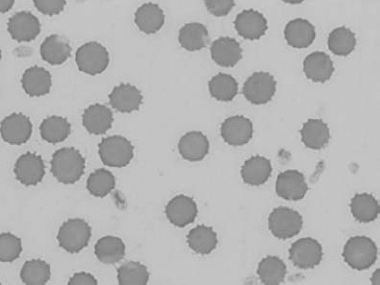

Figure 1.11 Canine blood film showing echinocytes III (also see color section).

Figure 1.12 Feline blood film showing echinoelliptocytes (also see color section).